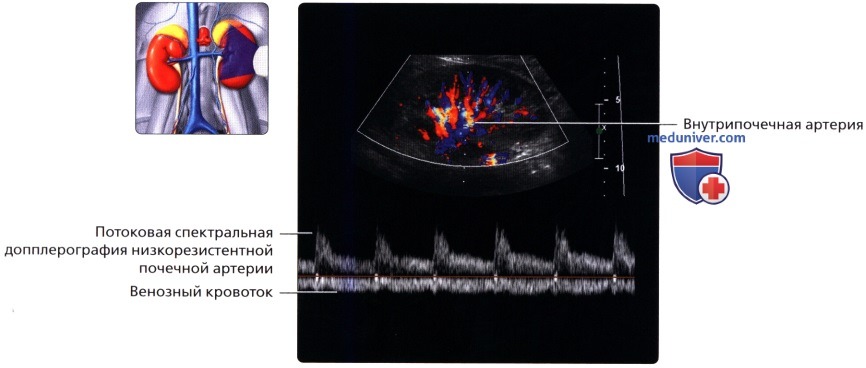

Неотъемлемой частью обследования почек стало ультразвуковое допплерографическое исследование, дающее возможность наблюдать за кровотоком в почечных сосудах. Делая УЗИ сосудов почек, можно установить на ранней стадии стеноз артерий, сбои в кровоснабжении, сосудистые сбои.

УЗДГ (УЗИ сосудов почек) выполняется в положении больного лежа на боку или сидя. Каких-то особенностей у этой процедуры нет. Врач также перемещает датчик по поверхности кожи пациента, внимательно изучая постоянно меняющиеся на мониторе изображения.

Ультразвуковое исследование при заболеваниях сосудов почечного кровообращения

К этим заболеваниям относятся поражения почечной вены и артерий. Это могут быть сужения (стенозы), закупорка тромбом (тромбозы), а также нарушение целостности сосудов при травмах.